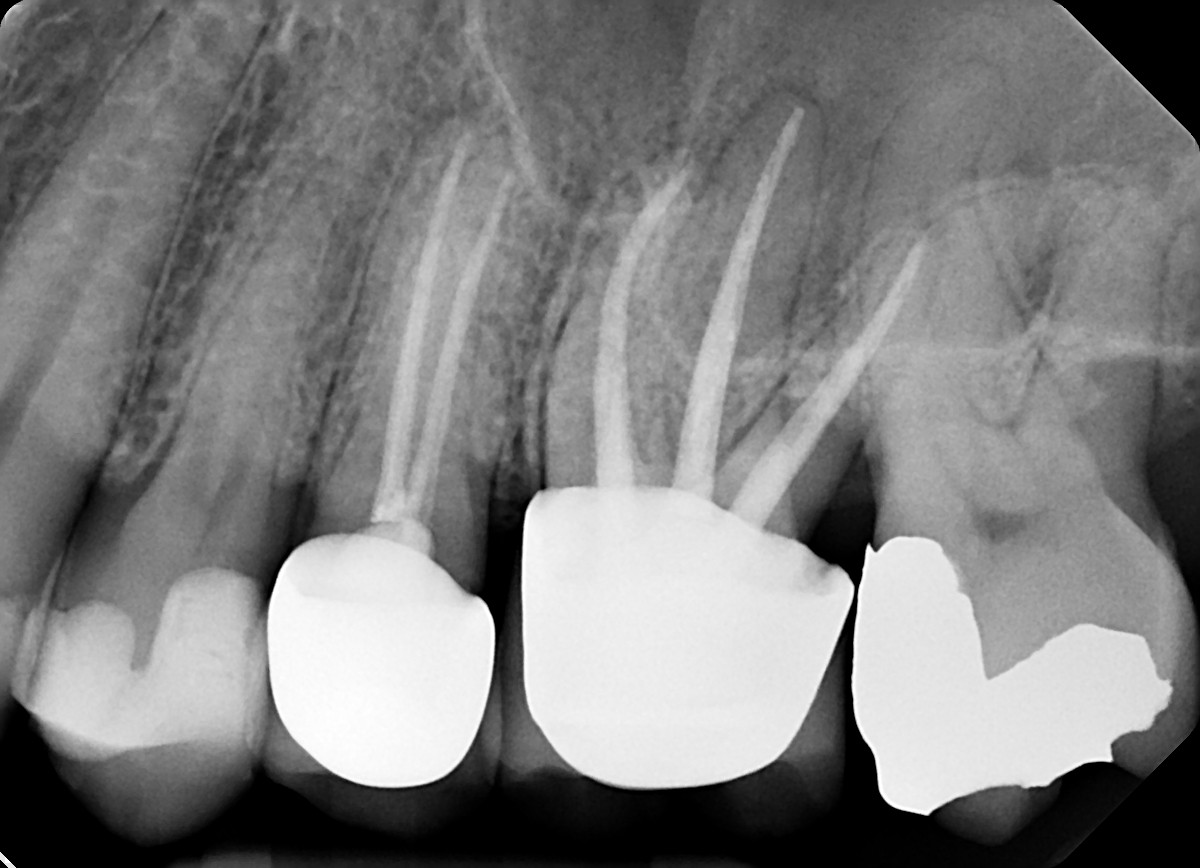

1. Evaluate the root canal treatment of tooth # 2.5?

2. What option cannot be selected for root canal treatment of tooth # 2.6?